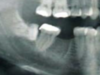

26

What radiographic sign is this showing in regards to M3M surgery risk to ID canal

Darkening of the root where crossed by the canal